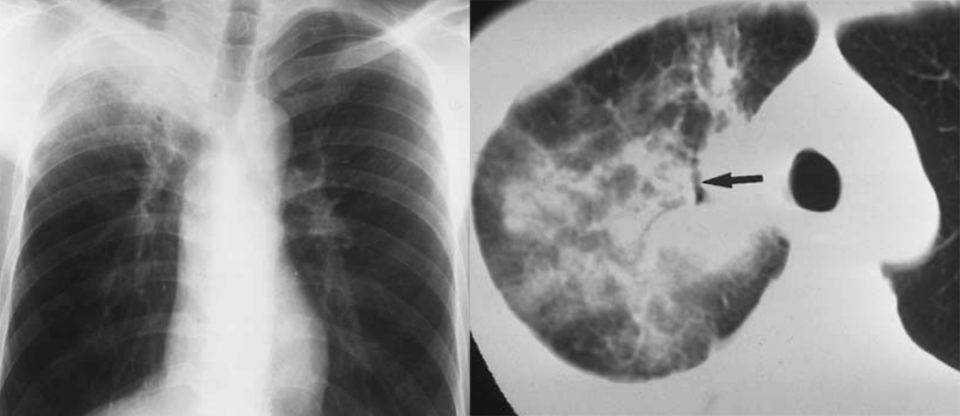

图片

男,38 岁。胃腺癌根治术后 4 年。1 年前的胸片显示右上肺片状边缘不清的病灶,怀疑结核,抗结核治疗无效。CT 显示右肺上叶实变应,周围伴磨玻璃密度,内部可见充气支气管征。穿刺活检证实。